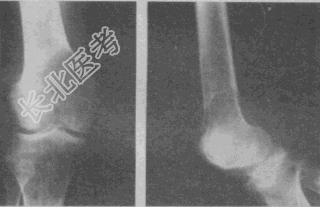

- 单项选择题女性,19岁, 右股骨下端疼痛3个月。X线片如图。诊断应考虑

A、骨肉瘤

B、软骨肉瘤

C、骨巨细胞瘤

D、纤维肉瘤

E、动脉瘤样骨囊肿